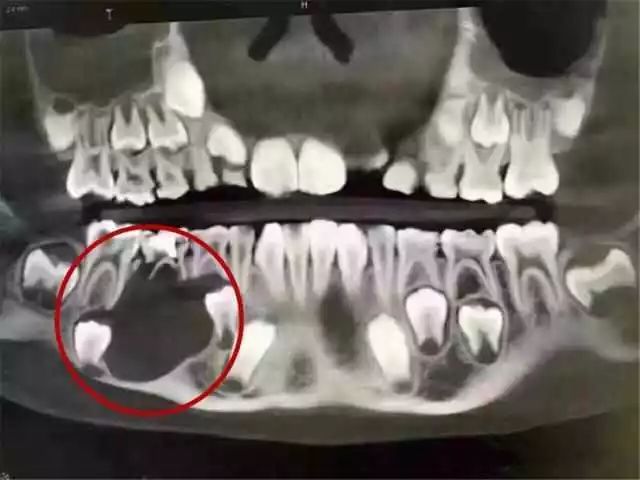

再看这位5岁小朋友的牙齿情况

这位5岁的小朋友,20颗牙齿8颗牙烂得只剩下牙根,而且牙根全部变成黑色,还有6颗是从牙根部断掉,嘴里光秃秃的,几乎看不到牙齿!